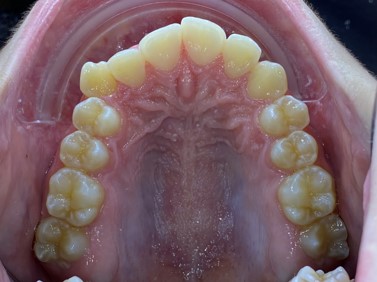

Chief complaint: We present the case of a 12-year-old female patient who came for an orthodontic evaluation, motivated by a family history of treatment. Clinical and radiographic analysis revealed a skeletal Class II malocclusion with molar and canine relationships also in Class II, moderate crowding in both arches, a deviation of the dental midline, and ectopic eruption of tooth 13. No functional issues with breathing or swallowing were observed, and oral health was generally good. A slight mandibular retrusion was noted in the soft tissue profile. A treatment plan was proposed using the Angel Aligner Pro system, aiming to correct dental misalignments and improve facial harmony through a minimally invasive, growth-adapted approach.

- Upper and lower dentoalveolar compression

- Moderate upper and lower crowding

We approached the case by combining upper distalization using the A8 protocol with an asymmetric virtual jump. In this way, we solved the crowding without proinclining the incisors and improved the anteroposterior relationship through the use of elastics. In the lower arch, we carry out a development of the posterior sectors prior to the resolution of the crowding, in order to avoid roundtripping and excessive IPR of the incisors. To achieve an effective extrusion and distalization of 13, we combine the use of direct bonding button on vestibular of 13, with angelButton elastics mesial and distal to the canine. These mechanics help to ensure that the extrusion is real and that the aligner always remains adapted.

In the upper arch, the main goal will be to correct the Class II malocclusion by distalizing the upper posterior teeth in order to resolve crowding without proinclining the incisors. This movement will be accompanied by an asymmetric “bite jump” of 1 mm, which will help improve the skeletal Class II discrepancy, promoting mandibular projection, especially considering that the patient is still in the growth phase. Additionally, bilateral and symmetric expansion will be planned until a torque of 0° is achieved, allowing for proper transverse alignment and greater stability of the final result. Lingual button cutouts will be placed on teeth 14 and 24 to facilitate the required movements. To optimize control and retention, vertical mesial beveled attachments, as large as possible, will be placed on the premolars and molars, as well as on teeth 12 and 22, reinforcing the mechanics in the anterior sector. The inclination of the central incisors 11 and 21 will be corrected according to the visual reference provided in the clinical image. Furthermore, it will be necessary to center the upper midline by shifting it 0.5 mm to the left to achieve greater aesthetic symmetry. As for the lower arch, treatment will begin with a phase of expansion and derotation of the posterior teeth, which will set the stage for subsequent movements in the anterior sector. Once this goal is achieved, alignment of the teeth from canine to canine will proceed, aiming to minimize anterior interproximal reduction (IPR) and avoid unnecessary round- tripping movements of the incisors. Vestibular button cutouts will be made on teeth 36 and 46, while teeth 37 and 47 will have horizontal attachments that will serve as anchorage to ensure stability during treatment.